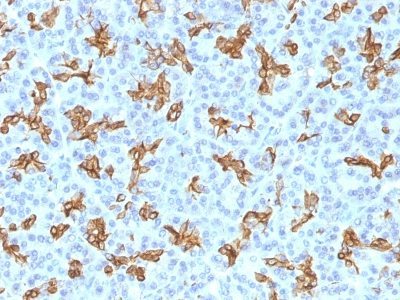

| Positive control | MCF-7, HeLa cells, Breast Cancer |

Recognizes a protein of 40 kDa, identified as cytokeratin-19 (CK19), which is expressed in sweat gland, mammary gland ductal and secretory cells, bile ducts, gastrointestinal tract, bladder urothelium, oral epithelia, esophagus, and ectocervical epithelium. Anti-CK19 reacts with a wide variety of epithelial malignancies including adenocarcinomas of the colon, stomach, pancreas, biliary tract, liver, and breast. Perhaps the most useful application is the identification of thyroid carcinoma of the papillary type, although 50%-60% of follicular carcinomas are also labeled. Anti-CK19 is a useful marker for detection of tumor cells in lymph nodes, peripheral blood, bone marrow and breast cancer.